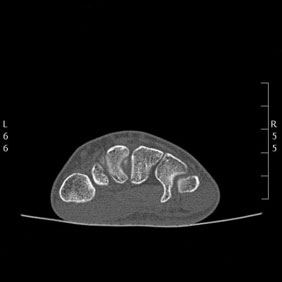

Tomografía computarizada Osteoarticular

< Volver a "Tomografía Computarizada (TC) con Inteligencia artificial"Con esta prueba valoraremos la patología de las vertebras, fracturas, hernias, protusiones discales, …